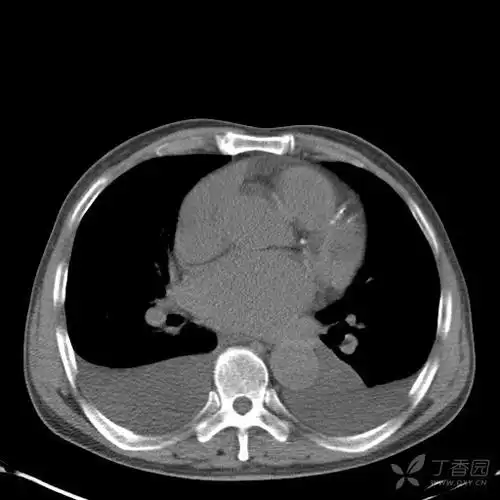

胸腔积液